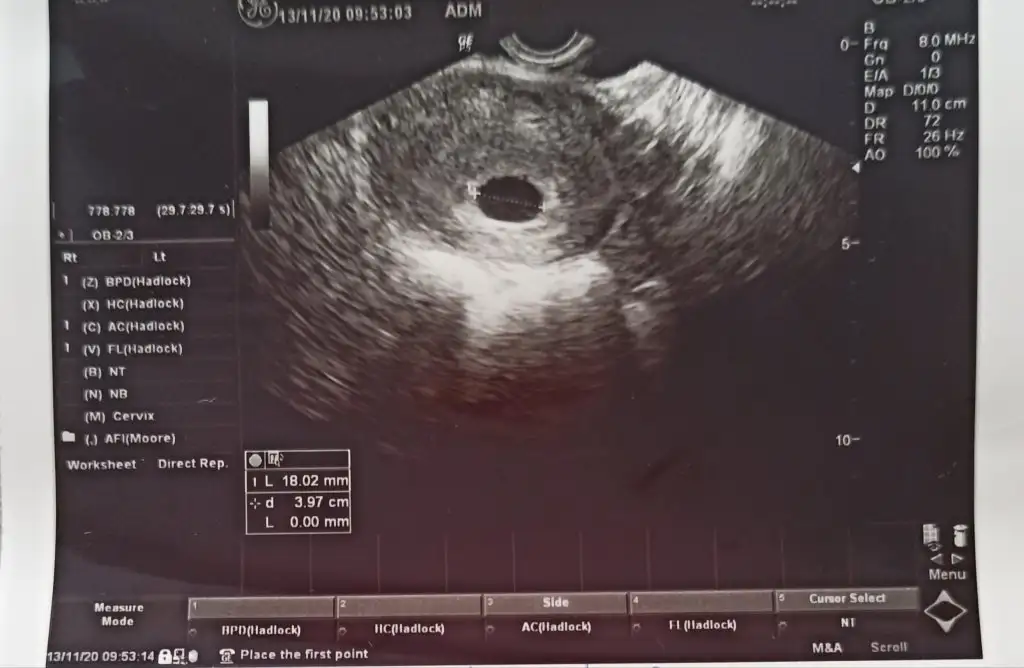

Kesen falan süper Yuvarlak görünüyor gelişiyor da Ama bi problem var benim kese 18 mm oldu yolk kesesi falan hiç gözükmüyor normal mi arkadaşlar ben çok üzülüyorum bugünden beri ya mahvoldum

Bir hafta daha bekleyelim geç döllenme olmuş ddi ama kesem büyük top gibi neden gözükmedi anlamadım.gec döllenme olsa kese de bu kadar büyümezdi öyle değil miDoktorunuz bişey söylemedi mi

Burda yolk olmalı ama doktorda demiş biraz daha sabret beklemekten başka çare yok Suan inşallah oluşurİki ultrason arasında 10 gün var kızlar en sonuncusu da 6+6 yim normalde

Bu da üstten ultrasonBurda yolk olmalı ama doktorda demiş biraz daha sabret beklemekten başka çare yok Suan inşallah oluşur